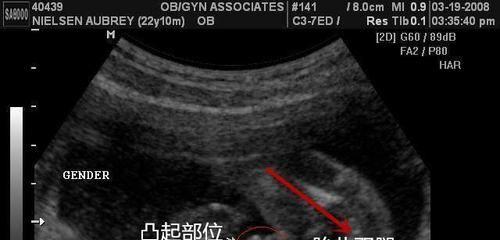

XY孕囊和XX孕囊形状大不同,长条形和圆形早已暗示胎儿性别

孕囊是受精卵分裂发育而来的小胚胎,在胎儿还没有完全形成的时候就以孕囊的形式存在,因此孕妇在前几次产检的时候都会检查孕囊的发育情况,从而判断胎儿是否在正常发育。孕..

早期孕囊形状看性别图片圆形是男孩这个说法准吗-数据对比一目了然

早期孕囊形状看性别图片圆形是男孩这个说法准吗-数据对比一目了然,是不准的,在医院或者生殖中心我们经常看到很多的准妈妈拿着B超单看了又看,还跟旁边的同来检查的孕妈一..